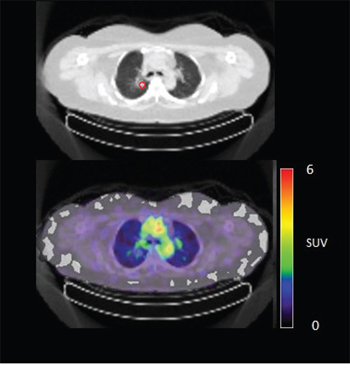

In 6 out of 10 patients, target lesions were visually assessed positive for 89Zr-cetuximab uptake. Figure 4A and 4B shows examples of visible 89Zr uptake in a metastatic lesion of the iliac bone (patient 8) and the lung (patient 10). In Figure 4C, another lung lesion in patient 10 shows no uptake. Most tumor lesions showed increasing uptake in time, indicating accumulation of cetuximab. SUVpeak of these lesions varied between 2.2–7.5 on day 6 p.i.. Figure 4D illustrates the photopenic aspect of liver metastases within normal liver tissue accumulating high amounts of 89Zr-cetuximab. Two of the 3 patients who were scanned at day 10 p.i. had visible 89Zr-cetuximab uptake. SUVpeak at day 10 increased compared to day 6 in patient 8 (from 7.3 to 10.3), but was comparable in patient 6 (3.17 and 3.36, Figure 4E Due to the physical half-life of 89Zr, image quality deteriorated over time, making day 6 p.i. the optimal scanning time point. Visually negative tumor sites had SUVmean of 1.0–1.9 at day 6 p.i. (Figure 5).

Figure 4C: 89Zr-cetuximab PET scan of patient 10 at day 6 p.i. without visible uptake in tumor lesion in the upper lobe of the right lung.

Of 6 patients showing 89Zr-cetuximab uptake, 4 had clinical benefit. When comparing patient 6, 9 and 10 who all had lung metastases showing uptake, only patient 9 and 10 had clinical benefit. The lack thereof for patient 6 may be due to the multiple lines of previous therapy including radiotherapy on the lung metastases compared to 1–2 previous lines of therapy for the other two patients leading to a potential difference in tissue architecture and cellular content of these lesions. The absence of response may also be due to N-RAS or other mutations, however, unfortunately no adequate tumor material was available for further assessment of the mutational status in these patients. One patient had clinical benefit, although 89Zr-cetuximab uptake could not be visualized. Possibly, the amount of cetuximab that reached the tumor was insufficient for visual assessment, but did induce anti-tumor activity, for example by antibody-dependent cell-mediated cytotoxicity [15]. For 7 patients with two lesions available for quantification only patient 10 showed heterogeneous uptake of 89Zr-cetuximab (Figure 4B and 4C). Although all lesions in this patient showed response to treatment, one of the lung lesion did not show visible uptake of 89Zr cetuximab. This might be caused by a difference in size, the negative lesion is smaller compared to the others and thereby relatively unfavorable for 89Zr PET imaging.